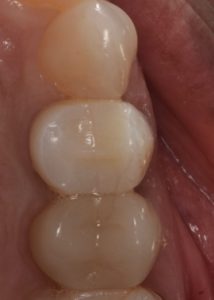

This video demonstrates alveolar ridge preservation following atraumatic surgical extraction of an endodontically treated tooth. Emphasis is placed on minimizing surgical trauma to preserve existing hard and soft tissues.

- Strategies to maintain ridge volume for future implant therapy